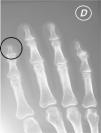

Hand radiographs showed bone resorption in the distal phalanx of the right index finger (Fig. 3).